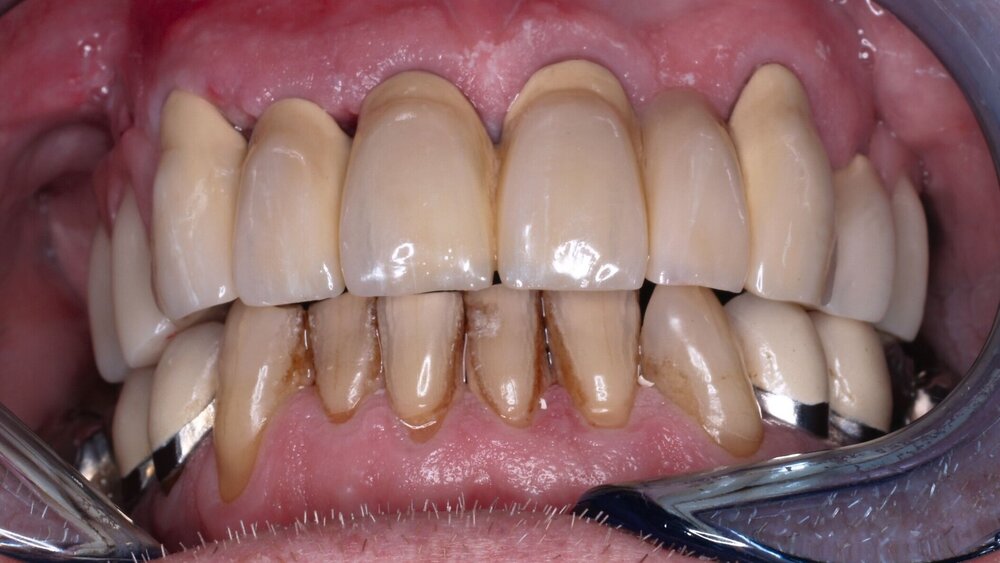

Der Patient stand unter der Dauermedikation von Metformin 500 mg, Ramipril 5 mg, Torasemid 10 mg, Metohexal 47,5 mg, Simvastatin 20 mg, Tamsulosin 0,4 mg und 3 mg Marcumar (INR 2,5–2,8) bei Zustand nach einer Bypass-Operation im Jahr 2019. Klinisch zeigten sich im Oberkiefer insuffiziente, verblockte und verblendete NEM-Kronen mit beidseitigen Gold-Extensionen distal, die über Geschiebe mit dem anterioren Anteil verschraubt waren (Abbildungen 1 und 2). Der Patient berichtete, dass die vorhandenen Kronen und Brücken 1984 eingesetzt worden seien.

Besonders auffällig war eine Dezementierung, die klinisch durch rechtsseitigen Druck und Zug mit einer Pinzette und daraufhin austretende Sulkusflüssigkeit in Regio 14 detektiert wurde. Da entsprechend des synoptischen Behandlungskonzepts [Naumann et al., 2010] bei prothetischer Neuversorgung eine gesamte Evaluation der Restpfeiler erfolgen muss, wurden zunächst die Kronen im Oberkiefer durch Schlitzen und Aufbiegen entfernt. Erst danach ließ sich deren Erhaltungswürdigkeit abschließend beurteilen.